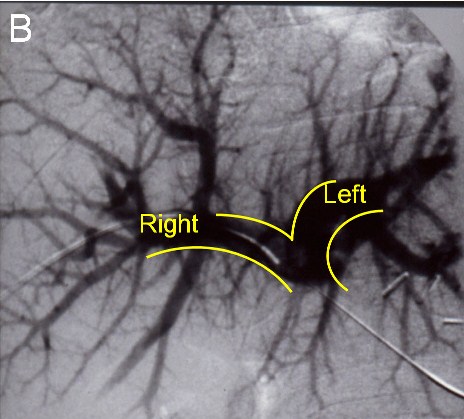

![]() |

(B) Before the next operation, a portal vein embolization is done: Venogram showing a normal portal vein prior to embolization |